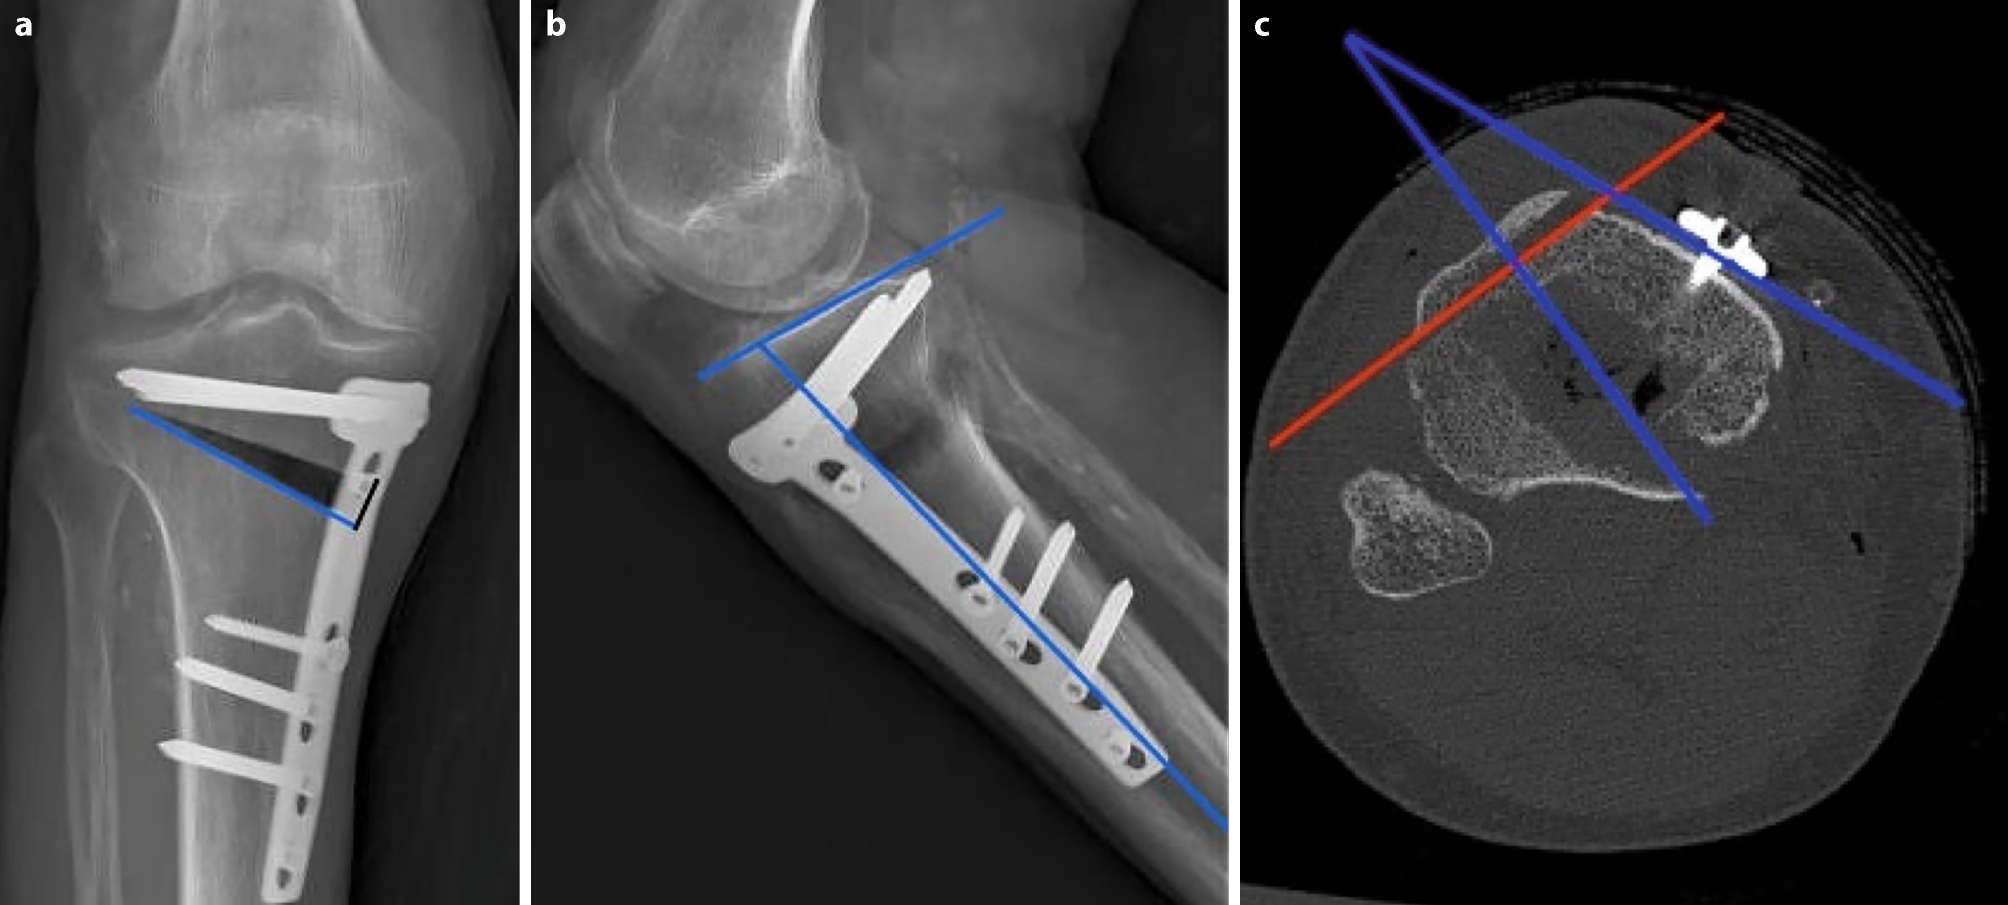

To establish exact representation of the osteotomy gap, a strict side profile view of the plate was achieved by internal rotation of the leg as well as flexion of the knee to compensate for the posterior slope of the tibia and the osteotomy itself (see Fig. 4). Best results were obtained with 30° of flexion (see Table 1). The mean osteotomy width was 12.5 mm (range 10.7–13.9 mm). The mean tibial slope was 10.3° (range 7.4–17.2°) and mean osteotomy slope was 17.2° (range 9.2–22.7°). The internal rotation offset of the plate measured in the axial CT scans showed a mean value of 25° (range 15–31.5°). The overlap of the tibial tuberosity is an obstacle for the evaluation of ossification in the central part of the gap, which can be overcome in the CT analysis (see Fig. 5). The CT scan was able to erase most of the metal artefacts and trabecular structure could be additionally displayed.

Fig. 4

a The conventional AP radiography of the cadaveric leg shows tibial overlap of the posterior tibia in the gap (b) exact representation of the osteotomy gap is achieved with 20° of internal rotation and 30° of flexion in the knee joint

When applying the X‑ray technique optimized in the cadaver (30° of flexion and 25° of internal rotation of the knee joint), 21 out of 36 X‑rays showed exact visualization of the osteotomy gap (Fig. 6).

Fig. 6

Radiological appearance of the osteotomy gap. a postoperatively, b 6 weeks postoperatively and c 12 weeks postoperatively with new bone healing spreading from lateral to the medial osteotomy side. The gap is visualized perfectly by flexion and inward rotation of the knee to rule out the overlap of the osteotomy gap and the plate